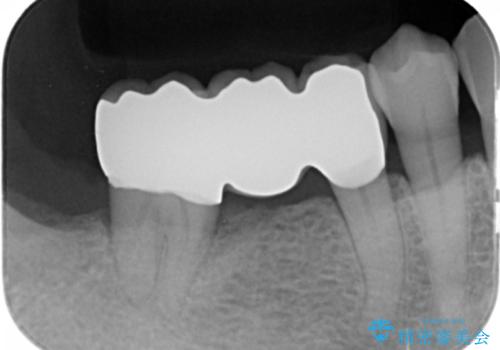

60代男性 奥歯のブリッジ 倒れこんでいる奥歯を部分矯正

親知らずを抜いて、倒れこんでいる手前の歯を矯正治療で移動させ、ブリッジにしました。

60代でしたが、歯もしっかり動いてブリッジを入れることができました。